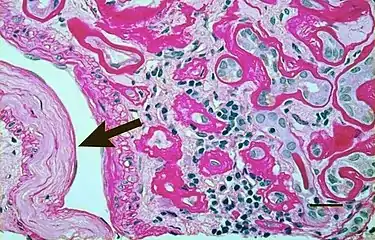

| Micrograph showing renal arterial hyalinosis – pink ring right-of-centre. PAS stain. | |

Light micrograph showing signs of hypertensive nephropathy: interstitial fibrosis, tubular atrophy with thickened tubular basement membranes, and fibrous intimal thickening of a small artery (arrow).